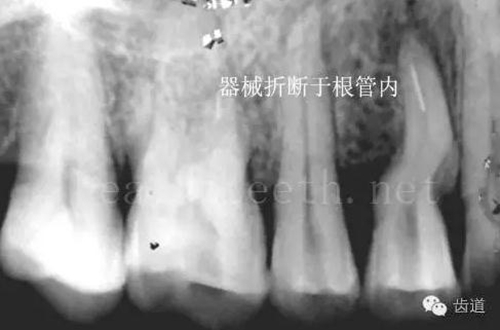

不良的根管充填治療

79.jpg